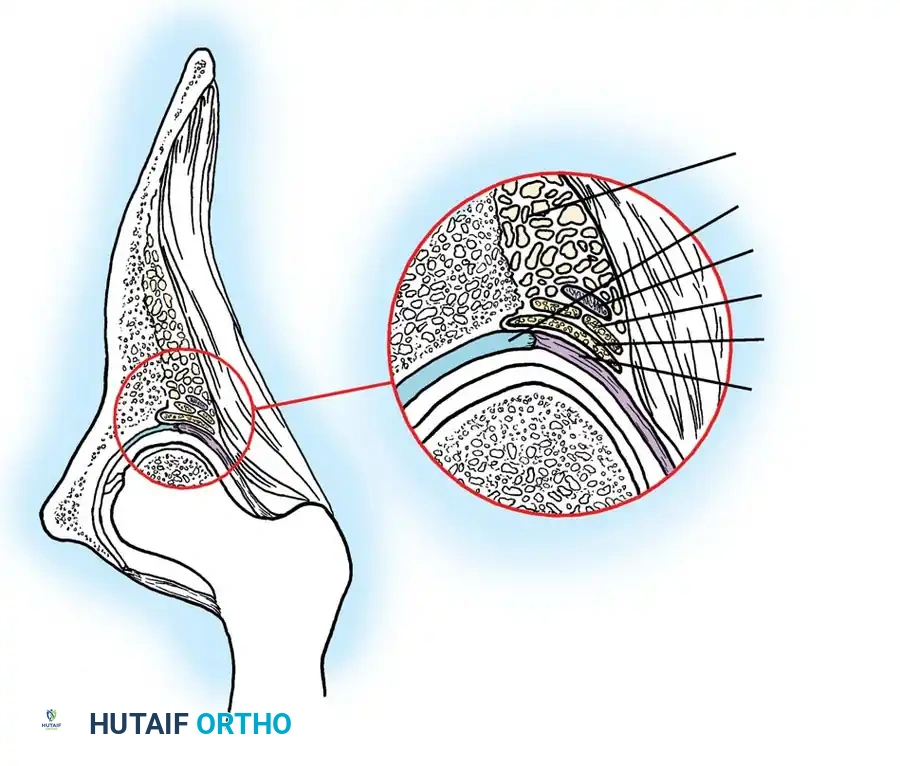

3. Arthrogram: Dye is injected to visualize the cartilaginous profile. Look for the "rose thorn" sign (limbus), the transverse acetabular ligament, and the ligamentum teres. Pooling of dye medially indicates an interposed pulvinar or inverted limbus preventing concentric reduction.

Intraoperative arthrogram demonstrating the cartilaginous contours of the femoral head and acetabulum during closed reduction.